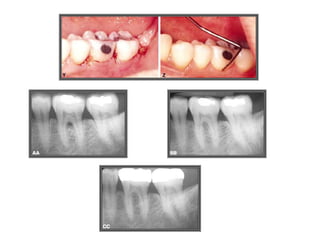

CASO 1

CASO 2

CASO 3

CASO 4